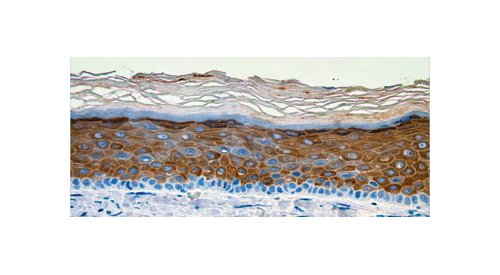

BASF e CTIBiotech desenvolvem modelo de pele humana produzido por bioimpressão em 3D, incluindo macrófagos...

A BASF Care Creations e a CTIBiotech anunciaram a criação dos primeiros modelos de pele produzidos por bioimpressão em 3D com a...